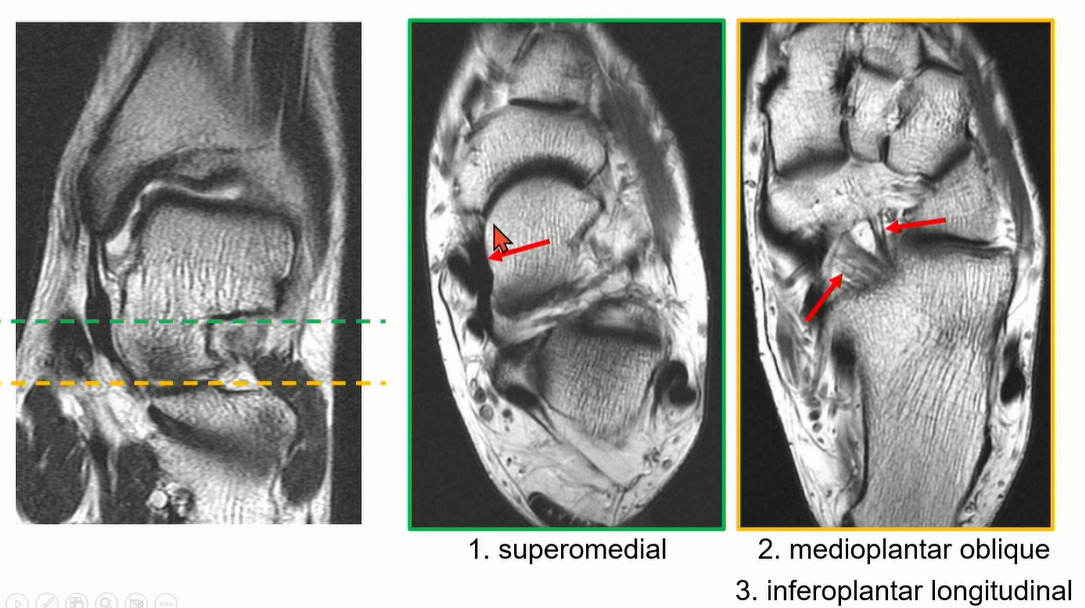

스프링 ligament는 plantar calcaneonavicular ligament라고 부르고, navicular tuberosity와 sustentaculum tali를 이어주는 인대이다. Medial longitudinal arch의 static stabilizer 중에 하나임. (다른 하나는 TP tendon )

Spring ligament는 1-3으로 구성되어 있다. complex임.